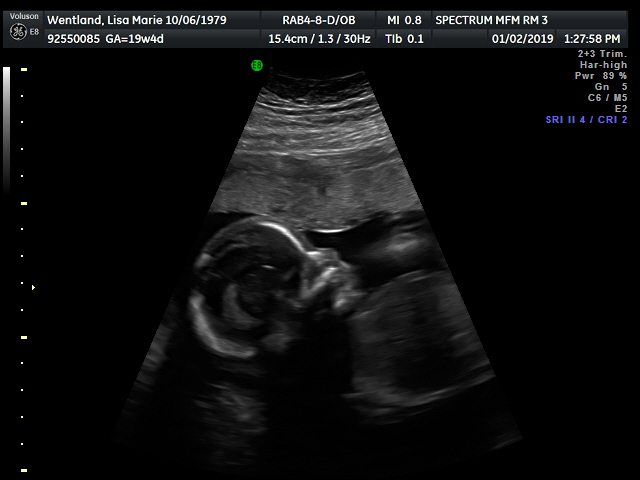

Baby #3. I had my anatomy scan on Jan 2 with the maternal fetal medicine doctor. He's currently breech and facing my spine. The scan took a while, but all looked good enough to cancel my consultation with the doctor afterward. Due to age, and other risk factors, I go back in for another ultrasound in 4 weeks to check growth.